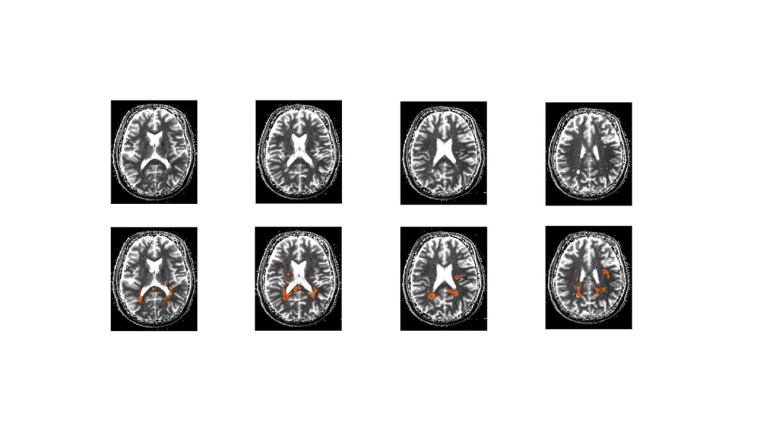

Die Messung des Myelinwasseranteils in Kombination mit biophysikalischer Modellierung stellt einen entscheidenden Fortschritt in der MS-Diagnostik dar.

Multiple Sklerose ist die häufigste neurologische Erkrankung junger Erwachsener und führt durch den Abbau der die Nervenfasern umgebenden Myelinschicht zu einer Beeinträchtigung der Signalübertragung im Nervensystem. Welche Methoden für die Erstdiagnose und die Bewertung des Krankheitsverlaufs und der Therapieerfolge eingesetzt werden können, lesen Sie in unserem Whitepaper zum Download.